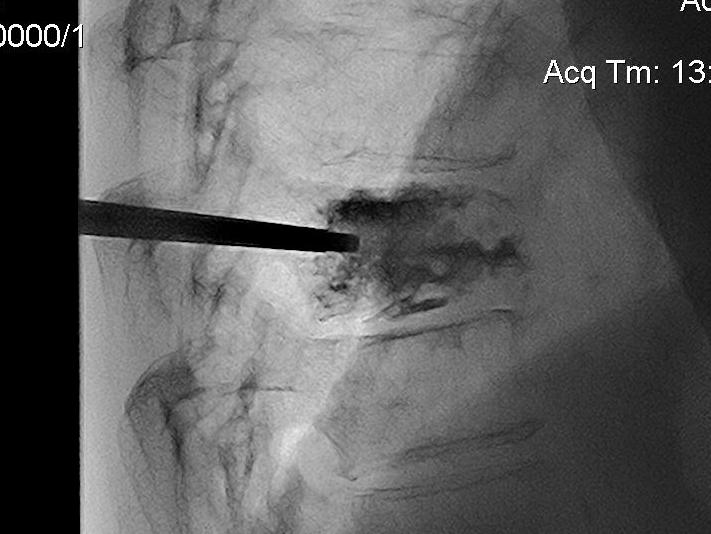

Technique

Percutaneous

- trochar into pedicle under fluoroscopy

- injection PMMA